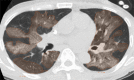

The coronavirus disease 2019 (COVID-19) pandemic is a global health care emergency. Although reverse-transcription polymerase chain reaction testing is the reference standard method to identify patients with COVID-19 infection, chest radiography and CT play a vital role in the detection and management of these patients. Prediction models for COVID-19 imaging are rapidly being developed to support medical decision making. However, inadequate availability of a diverse annotated data set has limited the performance and generalizability of existing models. To address this unmet need, the RSNA and Society of Thoracic Radiology collaborated to develop the RSNA International COVID-19 Open Radiology Database (RICORD). This database is the first multi-institutional, multinational, expert-annotated COVID-19 imaging data set. It is made freely available to the machine learning community as a research and educational resource for COVID-19 chest imaging. Pixel-level volumetric segmentation with clinical annotations was performed by thoracic radiology subspecialists for all COVID-19-positive thoracic CT scans. The labeling schema was coordinated with other international consensus panels and COVID-19 data annotation efforts, the European Society of Medical Imaging Informatics, the American College of Radiology, and the American Association of Physicists in Medicine. Study-level COVID-19 classification labels for chest radiographs were annotated by three radiologists, with majority vote adjudication by board-certified radiologists. RICORD consists of 240 thoracic CT scans and 1000 chest radiographs contributed from four international sites. It is anticipated that RICORD will ideally lead to prediction models that can demonstrate sustained performance across populations and health care systems.